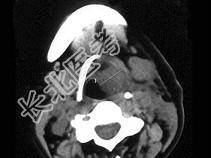

- 单项选择题女,54岁, 喉部异物感约3个月,PE: 左侧声带固定,可见肿物, CT如图,最可能的诊断是 ( )